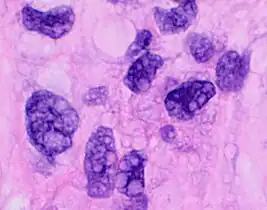

Micrograph showing contraction band necrosis, a histopathologic finding of myocardial infarction (heart attack).

In myocardial infarction

After a myocardial infarction (heart attack), no histopathology is seen the first ~30 minutes. The only possible sign the first 4 hours is waviness of fibres at border. Later, however, a coagulation necrosis is initiated, with edema and hemorrhage. After 12 hours, there can be seen karyopyknosis and hypereosinophilia of myocytes with contraction band necrosis in margins, as well as beginning of neutrophil infiltration. At 1 – 3 days there is continued coagulation necrosis with loss of nuclei and striations and an increased infiltration of neutrophils to interstitium. Until the end of the first week after infarction there is beginning of disintegration of dead muscle fibres, necrosis of neutrophils and beginning of macrophage removal of dead cells at border, which increases the succeeding days. After a week there is also beginning of granulation tissue formation at margins, which matures during the following month, and gets increased collagen deposition and decreased cellularity until the myocardial scarring is fully mature at approximately 2 months after infarction.[3]